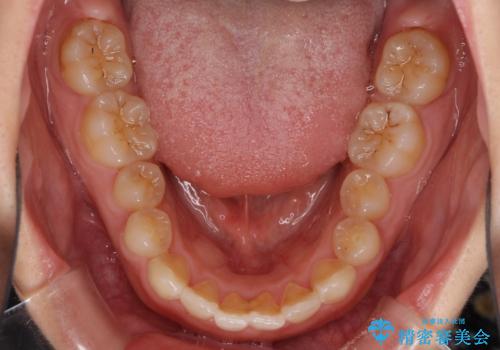

- 前歯のデコボコを治したいとのことで来院された患者様です。

上下顎ともに歯列全体の側方拡大とIPR(歯と歯の間を削る)によってデコボコが解消するように設計し、インビザラインにより治療を行うこととしました。